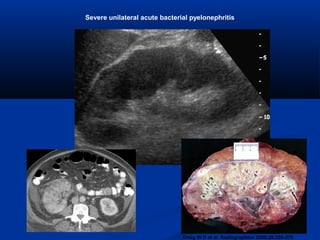

Severe unilateral acute bacterial pyelonephritis

• #8 Figure 4a.  Severe unilateral acute bacterial pyelonephritis. (a) US image demonstrates a slightly enlarged right kidney that is otherwise unremarkable, belying the advanced disease. (b) CT scan shows the enlarged kidney with global decreased uptake of contrast material and multiple small low-attenuation foci from abscess pockets, findings that prompted nephrectomy. (c) Photograph of the resected gross specimen reveals multiple intrarenal abscesses that have begun to partially coalesce. Scale is in centimeters.